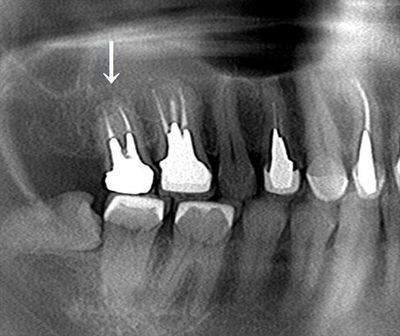

レントゲン写真です。

矢印部分が右上第二大臼歯であり、長いメタルコアが入っていることが判ります。